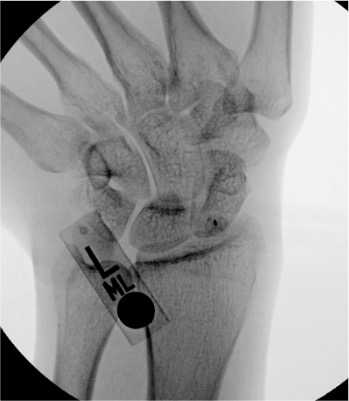

| Wrist | 1–3 mL | Fluoroscopy | Dorsal approach to radiocarpal joint | Lister's tubercle as dorsal reference landmark; radiocarpal joint just distal to radius on AP fluoroscopy; note multiple compartments — radiocarpal, midcarpal, and DRUJ each separate and may require individual injection for arthrography |

Wrist

Needle placementPost-injection